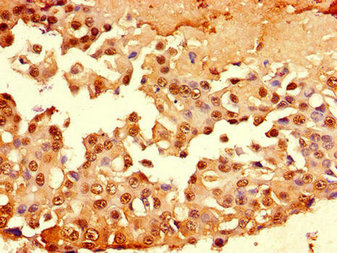

Immunohistochemistry of paraffin-embedded human breast cancer using CSB-PA11319A0Rb at dilution of 1:100